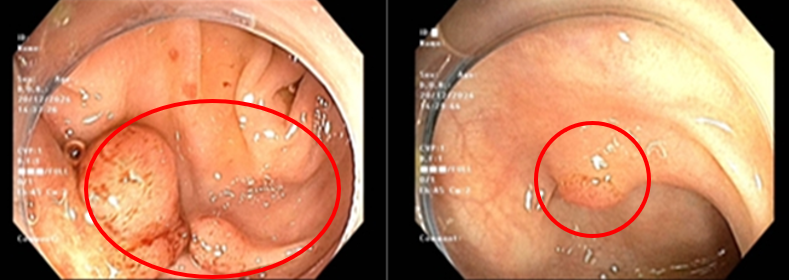

Cách vào viện 1 tháng, bệnh nhân xuất hiện đau tức vùng thượng vị, đau âm ỉ, không lan, đau tăng khi đói, kèm them ợ hơi, ợ chua, không nôn, không buồn nôn, đại tiểu tiện bình thường. Bệnh nhân đi khám được nội soi dạ dày thấy hình ảnh mặt sau hang vị có khối tổn thương nổi gồ kích thước khoảng 0.8cm, sinh thiết cho kết quả viêm teo niêm mạc dạ dày mạn tính hoạt động nhẹ, dị sản ruột, loạn sản độ thấp, Helicobacter Pylori (HP) âm tính. Nội soi đại tràng thấy 4 polyp, kích thước lớn nhất khoảng 1,5cm và có tổn thương dạng lõm kích thước khoảng 1,2cm. Bệnh nhân được cắt polyp cho kết quả giải phẫu bệnh là u tuyến ống, loạn sản độ thấp.

Hình 1: Hình ảnh polyp ở đại tràng

Sau đó bệnh nhân được nội soi cắt hớt dưới niêm mạc (ESD-Endoscopic Submucosal Disection) tổn thương đại tràng cho kết quả giải phẫu bệnh ung thư biểu mô tuyến biệt hóa vừa xâm nhập lớp hạ niêm mạc, diện cắt đáy còn u, diện cắt bên không còn u.